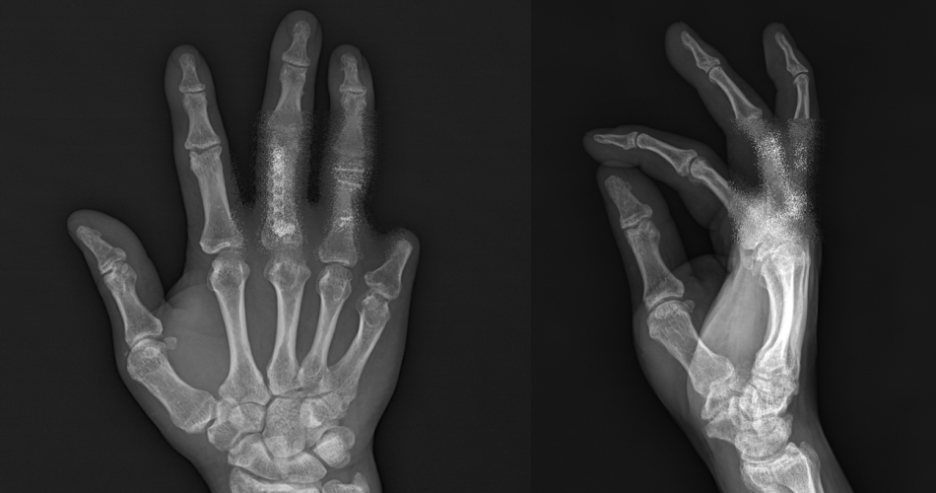

손가락 장애는 주로 산업현장이나 일상생활에서 예기치 못한 사고로 발생합니다. 우리 손가락에는 중수지관절, 근위지관절, 원위지관절이라는 세 개의 중요한 관절이 있는데, 이 관절들이 제대로 움직이지 못하거나 아예 절단되는 경우를 손가락 장애라고 합니다.

가장 흔한 발생 원인으로는 공장에서 일하다가 낙하물에 맞거나 금속 조각에 베이는 사고, 롤러나 프레스 기계에 손가락이 끼이면서 발생하는 압궤손상, 그리고 절단장비에 의한 손목이나 손가락 절단사고 등이 있습니다. 이러한 사고는 순간의 부주의로도 발생할 수 있어 더욱 안타까운 경우가 많습니다.

최근 상담을 받은 의뢰인의 사례를 살펴보겠습니다. 이분은 자동차부품 생산공정에서 유압기에 의한 압궤사고를 당하셨습니다. 오른손 엄지의 인대가 파열되고, 2번째부터 4번째 손가락의 근위지와 신전건이 파열되었으며, 새끼손가락은 개방성 골절로 인해 절단되는 심각한 상해를 입으셨습니다.

산업재해 요양이 종료된 후 1년이 지난 현재, 손가락 기능의 큰 변화는 없으며 통증과 저림 증상도 지속되고 있는 상태입니다. 이런 경우 정확한 운동범위 측정을 통해 장애등급을 판정하게 됩니다.

전문적인 측정을 통해 각 손가락의 상태를 확인한 결과는 다음과 같습니다. 엄지손가락은 다행히 정상 기능을 유지하고 있었습니다. 하지만 검지의 경우 근위지관절 운동범위가 75% 감소하여 심각한 기능 저하를 보였습니다.

중지는 근위지관절 운동범위가 70% 감소했고, 약지도 중수지관절이 약 67%, 근위지관절이 70% 각각 감소한 상태였습니다. 가장 심각한 것은 새끼손가락으로, 근위지관절과 원위지관절이 완전히 절단되어 해당 관절의 기능이 100% 소실된 상태였습니다.